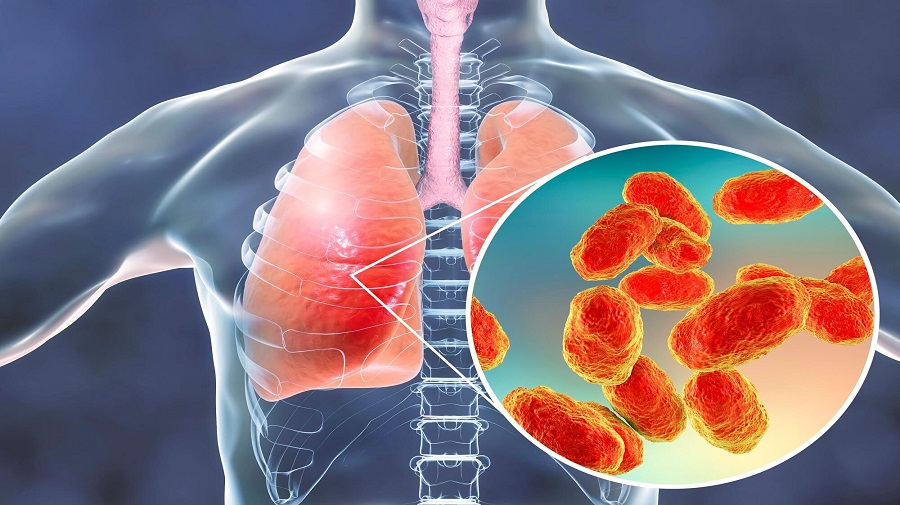

Медицинская тема: легочные осложнения при пневмонии